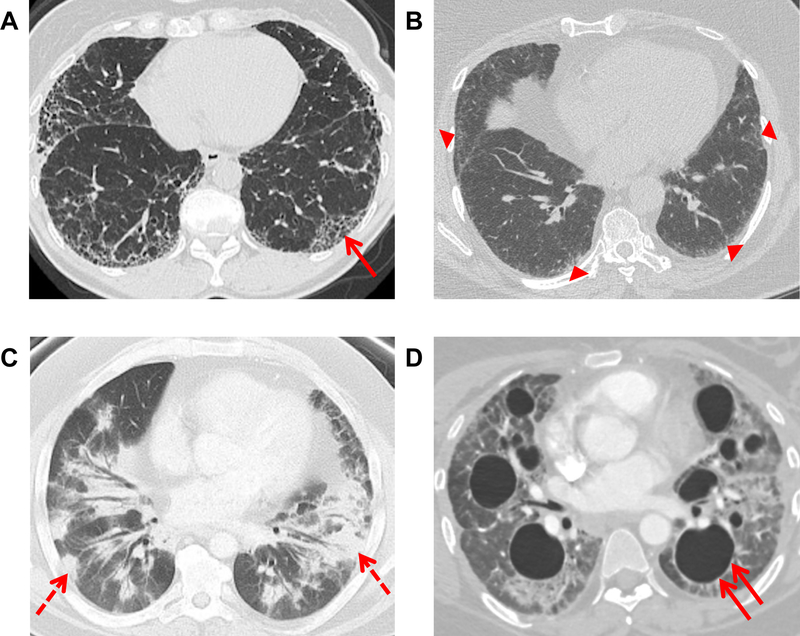

A forma mais comum de doença pulmonar causada pela AR é a doença pulmonar intersticial (DPI), causada por inflamação do parênquima pulmonar seguida de fibrose.

Entre os subtipos de DPI, são mais frequentes a pneumonia intersticial usual (PIU) e a pneumonia intersticial não específica (PINE). O padrão PIU é mais frequente em pacientes mais velhos, do sexo masculino, com história de tabagismo e traz um prognóstico pior com taxas de sobrevida mais baixas em comparação a outros subtipos de DPI.

Os sintomas mais comuns relacionados à DPI na AR são inespecíficos, como tosse e dispneia aos esforços e dor torácica pleurítica, requerendo um bom diagnóstico diferencial com outras doenças. No exame físico, podem ser auscultados sibilos ou estertores e observados sinais indiretos de doença pulmonar restritiva, como baqueteamento digital ou insuficiência cardíaca direita, que seria ocasionada por hipertensão arterial pulmonar.